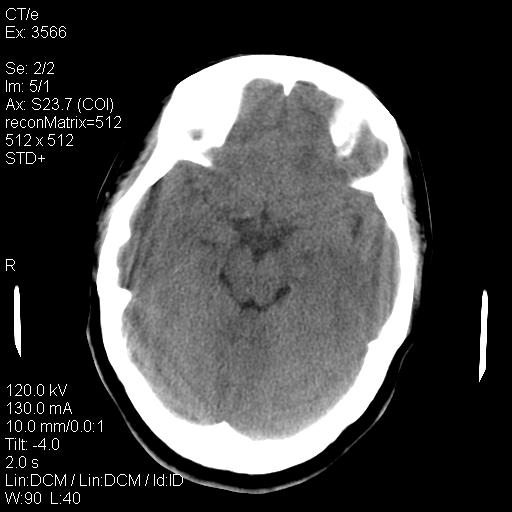

标题: CT9947:女,20岁,妊娠9个月,突然癫痫症状 [打印本页]

标题: CT9947:女,20岁,妊娠9个月,突然癫痫症状

双侧脑白质缺血缺氧性改变,并高度可疑“蛛网膜下腔出血”。

后可复性脑病,

考虑 妊娠子痫或妊高征

双侧脑白质缺血缺氧性改变.

考虑先兆子痫\\子痫致he,建议mri除外有无合并静脉窦血栓形成.

考虑pres

的确应该考虑可逆性后部脑病综合症--pres。感谢天南地北老师的指引,又学了一招儿,开心,呵呵!

考虑可逆性后部脑病综合症

支持pres